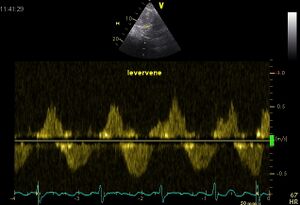

Flow pattern

Because in most cases VCI is perpendicular to the beam in the ultrasound image running, the flow pattern of the hepatic vein viewed . This is the same as VCI, only the hepatic vein is parallel to the sound beam .

Levervene02.jpg Hepaticveinrefersal01.jpg

Normal hepatic vein flow Systolic flow reversal of the hepatic vein in severe TI1